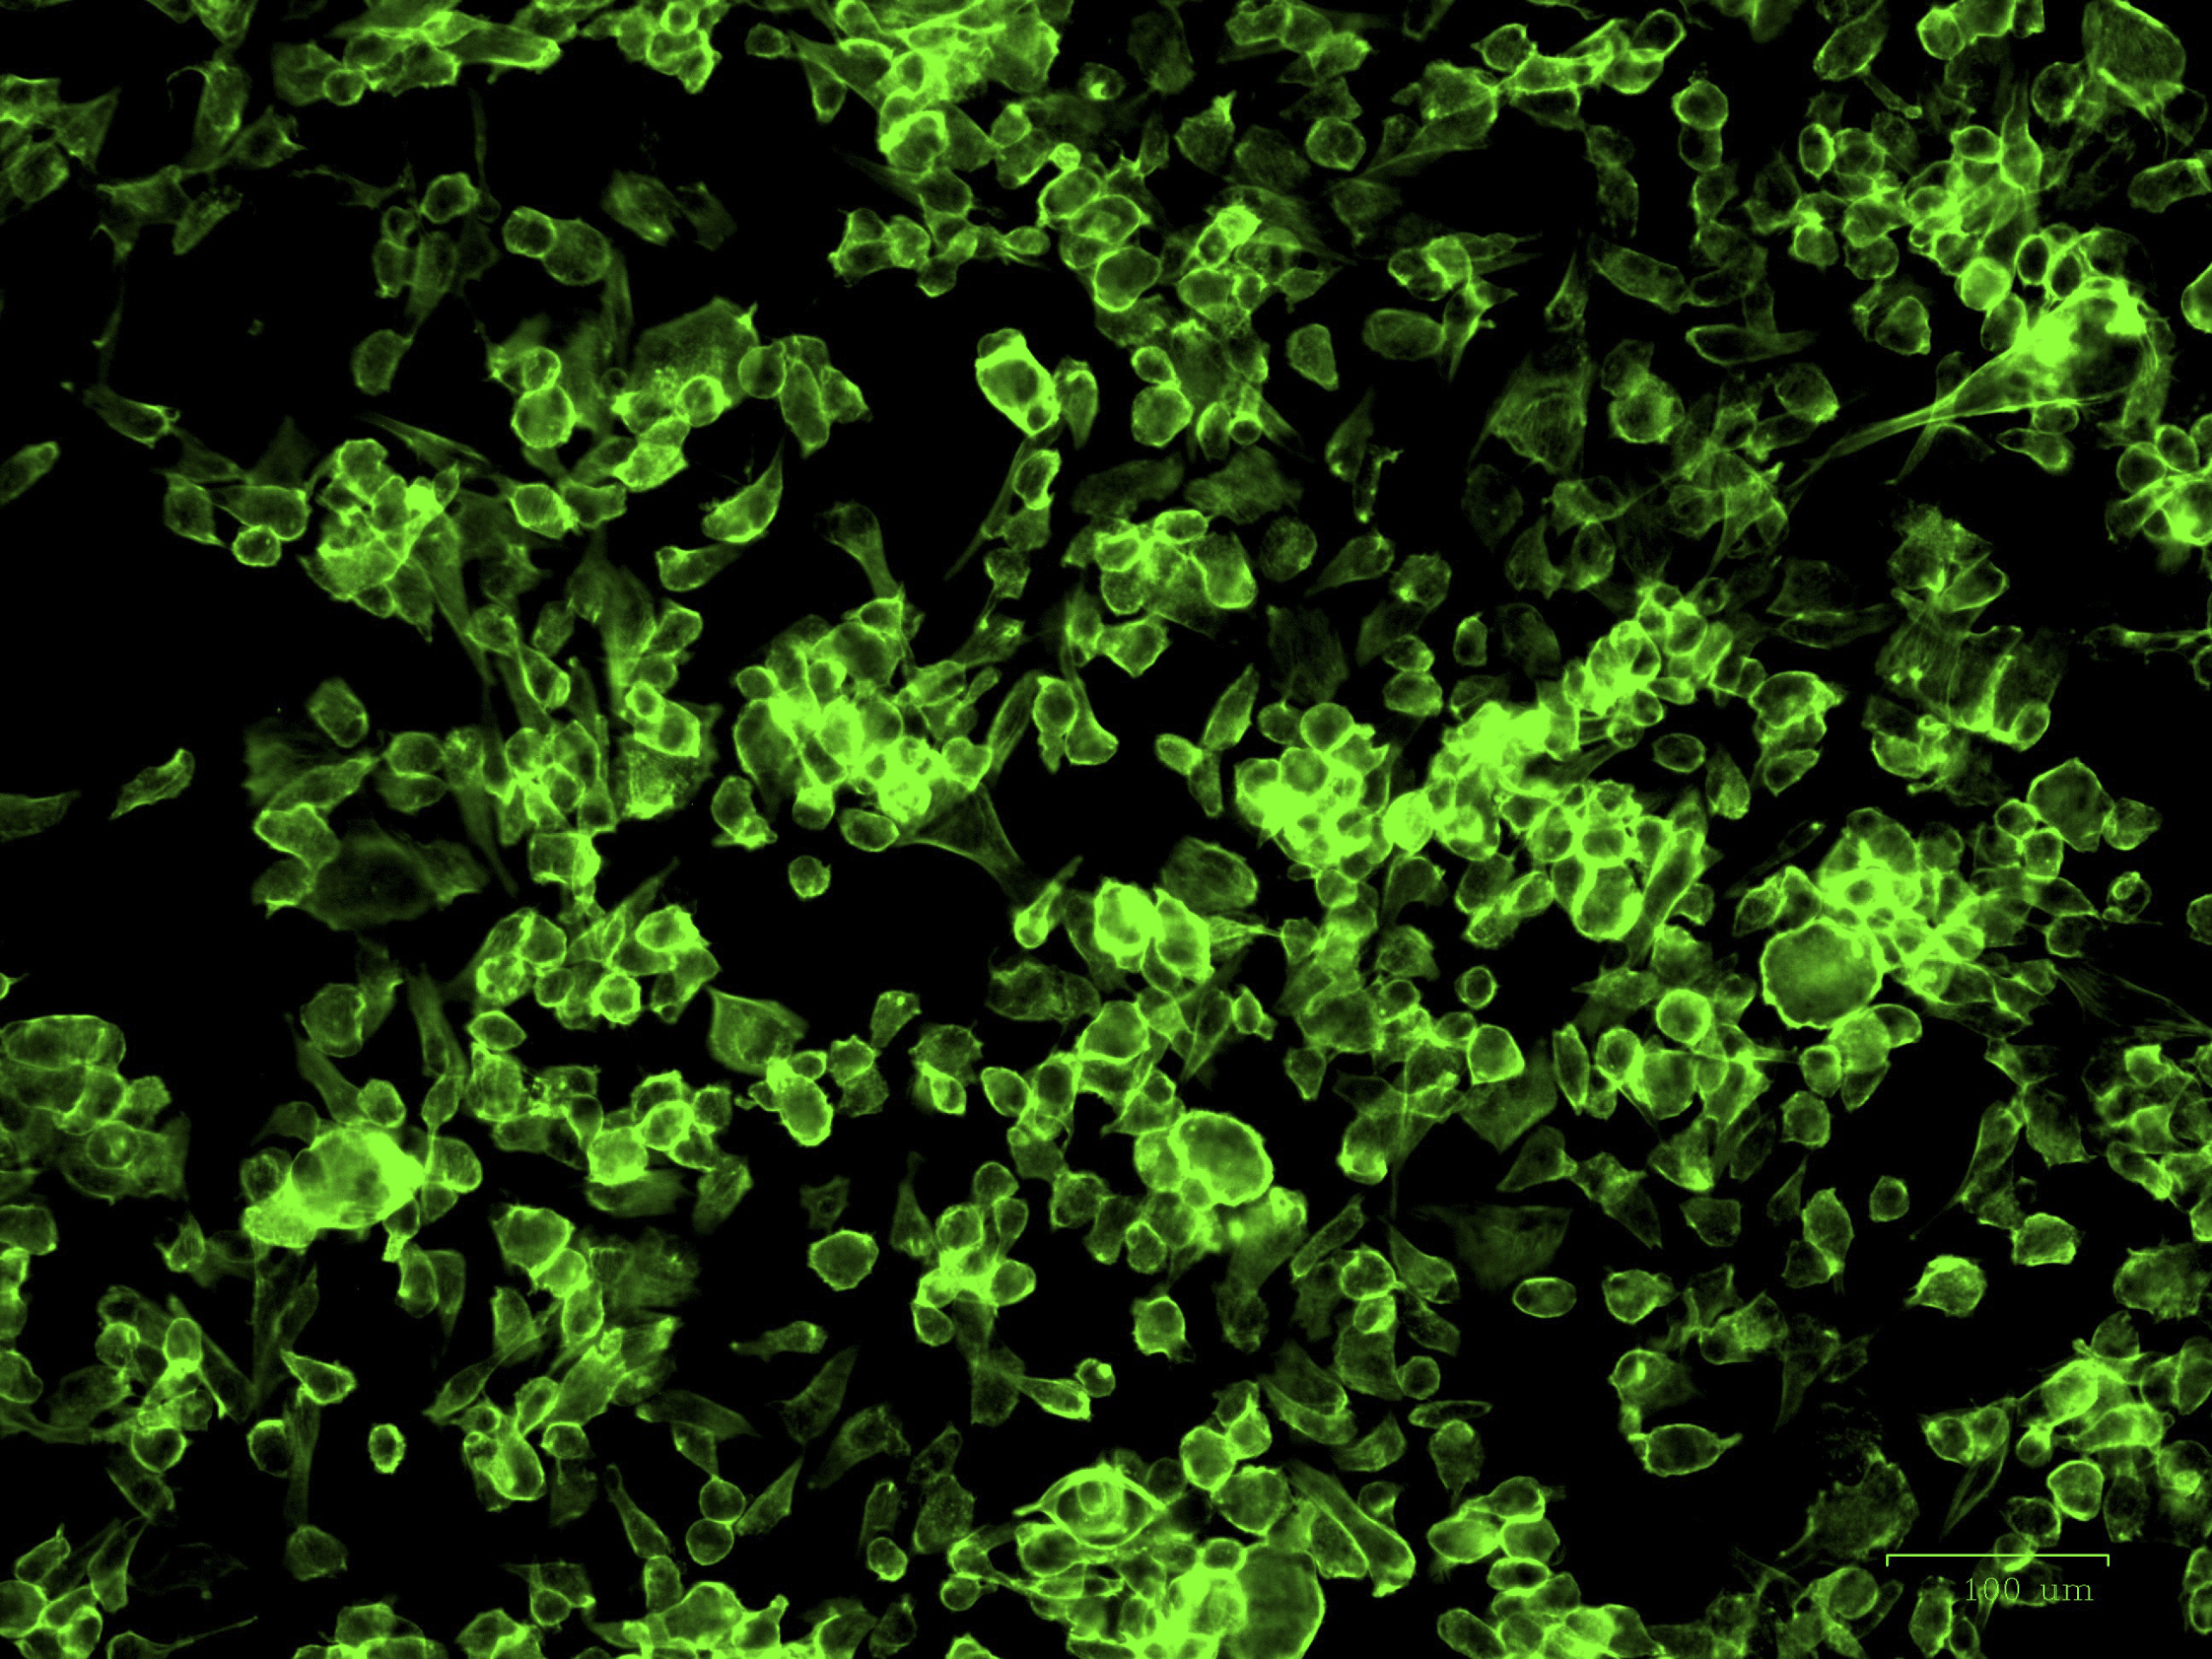

IN VITRO AND SILICO ANTIVIRAL SCREENING

In vitro and in silico evaluation of selected metabolites against Canine (CCoV) and Feline (FCoV) Coronaviruses.